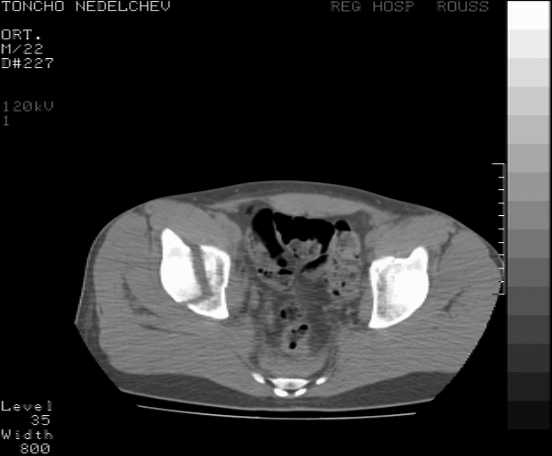

The details of the fracture are not so clear from the images sent...would you be able to send along an AP and Judet images as well as some additional axial images above and below the joint?

I’m not so sure that your patient has a Tr+PW pattern based on the images sent...maybe the fracture’s exact name won’t matter in the long run, but it’d be great to see enough images to make an accurate comment.

Here are some more axial images. What is your opinion as for the timing of the operative treatment?